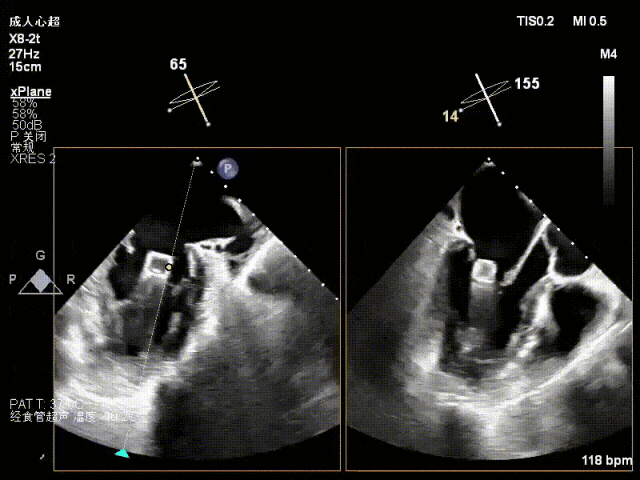

术中超声要点:

术前术后对比图:

术前

术后

术后,出院检查报告显示夹子位置固定,无移位,二尖瓣轻度反流,左室大小和LVEF值正常范围,左室壁运动分析未见明显异常。术后两个月随访检查,状态稳定,夹子位置固定,二尖瓣轻度反流,左室大小和LVEF值正常范围,左室壁运动分析未见明显异常(左室壁运动记分指数1分)。